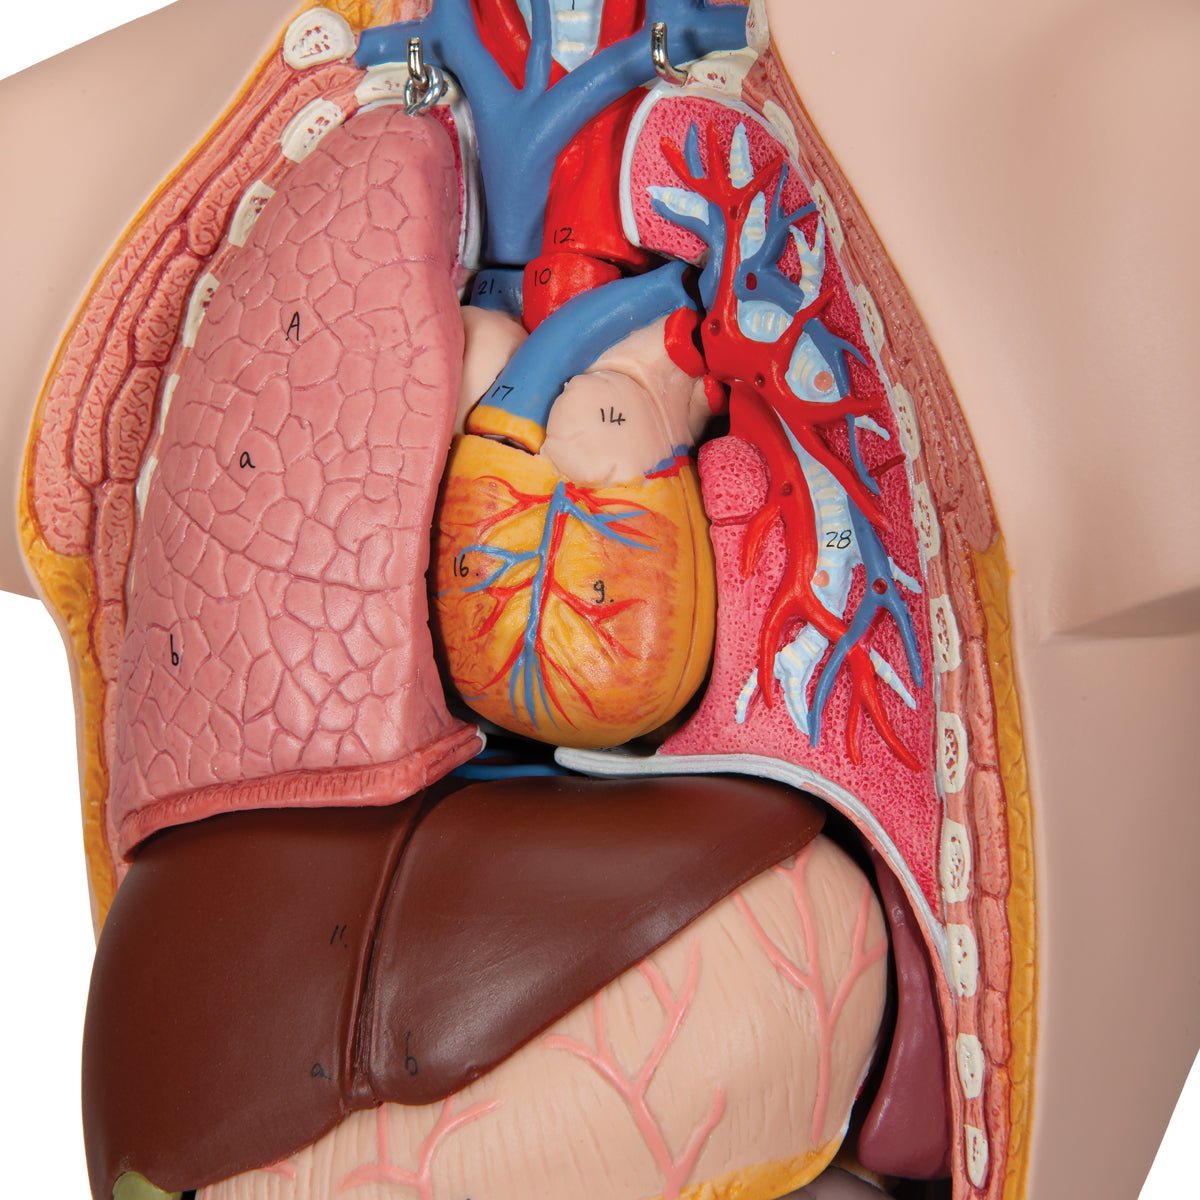

Salg af anatomiske modeller er det bærende element i eAnatomi, selvom vi også bruger mange ressourcer på at udvikle vores egne anatomiske materialer som fx plakater. Anatomiske modeller anvendes til forskellige formål og kan både vise afgrænset væv, organer samt organsystemer. Søger du en simpel model af knoglevæv eller måske en avanceret torso-model baseret på MRI teknologi, kan du finde det hele på eanatomi.com.